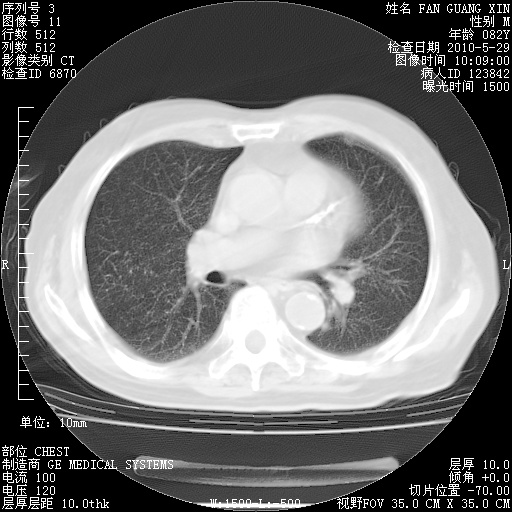

再治疗10天后的肺部CT